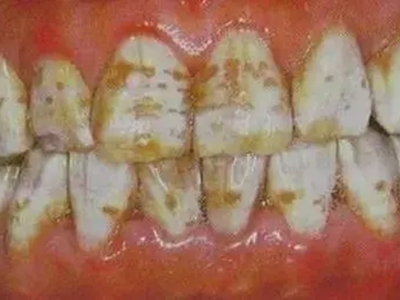

牙釉质发育不全牙齿表面棕色有坑图

牙釉质发育不全导致牙釉质表面呈棕褐色,有带状、窝沟状凹陷,以及黑点,牙釉质大面积缺损,牙齿表面变得粗糙,可出现进食时敏感等不适。

牙釉质发育不全牙面上棕色小坑图

重度牙釉质发育不全患者牙面出现带状或蜂窝状棕色小坑,累及多个牙齿,无明确的分布规律,严重影响牙齿美观,建议通过牙齿修复治疗恢复牙齿外观。

牙釉质发育不全牙齿中间有棕色条纹图

重度牙釉质发育不全患者牙齿表面呈棕褐色,牙釉质大面积缺损,其上有并列的条状凹陷,部分牙尖缺损,导致咬合关系被破坏,并出现疼痛等自觉症状。